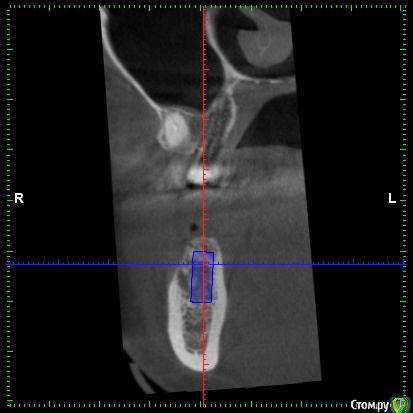

DenisV Опубликовано 22 мая, 2018 Поделиться Опубликовано 22 мая, 2018 Уважаемые коллеги, подскажите советом, допустимо ли с вестибулярной стороны 1.5мм кортикальной кости, или лучше НКР? на фото имплант 4.3*10? Ссылка на комментарий